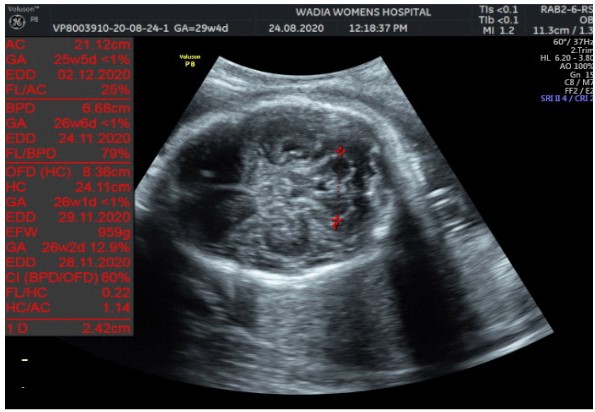

In the third conception during the COVID-19 pandemic, the couple presented to us in the third trimester. Anomaly screening ultrasound at 18 weeks done elsewhere was unremarkable, but subsequent scan done at our institute at 29 weeks was suggestive of fetal biometry corresponding to 26 weeks, head circumference below 1st centile, composite growth along 3rd centile. The fetus had microcephaly and sloping forehead; head circumference measured 241 mm (less than 1st centile for gestational age) (Figure 1). Transcerebellar diameter measured 23.6 mm (<1st centile) with vermis spared suggestive of cerebellar hypoplasia (Figure 2). The Cavum Septum Pellucidum (CSP) was enlarged measuring 22 mm x 10 mm (Figure 3). Additional ultrasound findings were corpus callosum agenesis, kinked thalami, widened subdural spaces and right club foot (Figure 4). The ultrasound differentials were pontocerebellar hypoplasia or Walker Warburg syndrome.